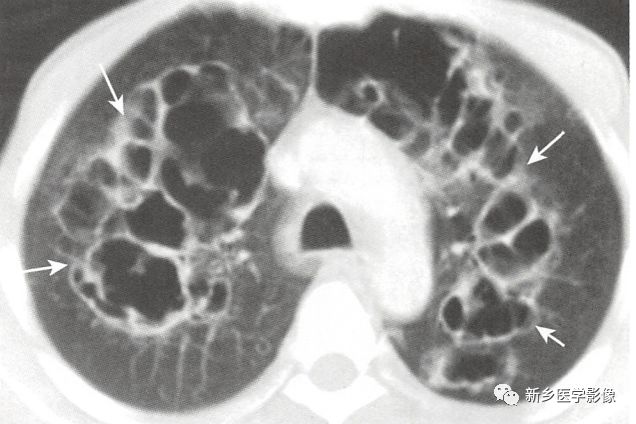

3种最常见的肺空洞性病变,常常可通过空洞壁的厚度、内缘平滑度和壁结节鉴别。

A、鳞状细胞支气管肺癌形成的是厚壁空洞(白色实线箭头),内有壁结节(黑色实线箭头)。

B、肺结核空洞壁相对较薄,位于肺上叶,内壁光滑(白色实线箭头)。

C、葡萄球菌肺脓肿表现为特征性厚壁(白色实线箭头),该例患者空洞很小,且内壁光滑(黑色实线箭头)

空洞的3种常见病因(癌、脓肿、结核)的区别: